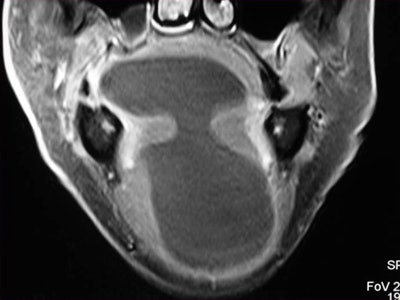

CT and MR are currently the primary imaging modalities to assess the oral cavity. CT is preferred in patients presenting with infectious/inflammatory syndrome. According to Borges, in patients presenting with oral cavity cancer, the use of dental CT software with the acquisition of para-axial and parasagittal high-resolution images in bone algorithm is most valuable in depicting early cortical bone erosion. MRI provides better soft-tissue resolution, and is the first choice in evaluating the deep extent of tumors and for the management of patients presenting with submucosal lesions.

Referring to the choice of imaging technique, she highlights the importance of considering different patients' specificities. Heavy smokers and drinkers prone to salivary stasis, difficulty in swallowing, and dyspnea are not good candidates for MRI, as this technique is very prone to motion artifacts, and patients with many dental fillings and/or dental implants may do better with MRI than with CT, she explained.

In terms of technical issues to note when imaging the oral cavity, Borges has plenty of good advice. She points out that dental-related artifacts can be avoided by angling the axial sections parallel to the dental fillings on CT or opting for MRI. When lesions are located in the gingival sulcus, jugal or palatal mucosa, or the tongue, cheek puffing is very helpful to clearly depict the full extent of the lesion and separate the lesion from the adjacent mucosal surfaces, she noted.

Finally, she emphasized that when using MRI, it is crucial to instruct a patient not to swallow and to breathe quietly during the entire examination. The use of surface coils can be very helpful for the imaging of superficially located lesions such as the parotid and submandibular glands and the floor of the mouth.